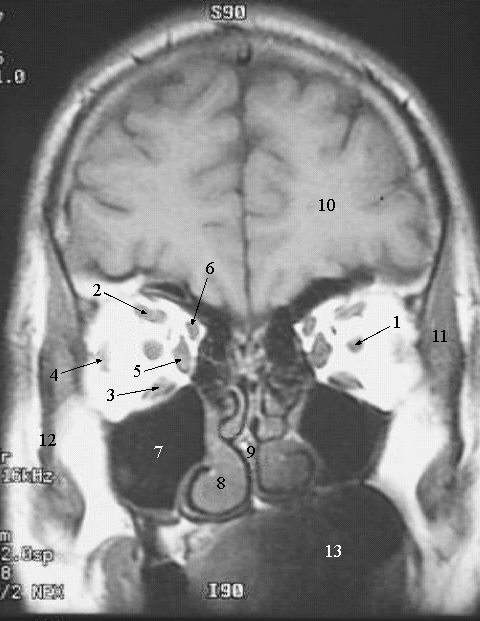

Head & Neck: Head MRI Coronal:

1. Optic nerve

2. Superior Rectus Muscle

3. Inferior Oblique Muscle

4. Lateral rectus muscle

5. Medial Rectus Muscle

6. Superior Oblique Muscle (belly)

7. Maxillary Air Sinus

8. Inferior Nasal Concha

9. Nasal Septum

10. Brain

11. Temporal Muscles

12. Ramus of Mandible

13. Oral Cavity.